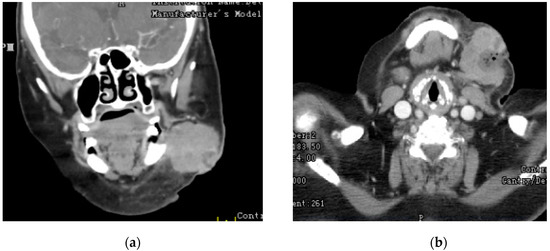

We present a case of a 78 year old Caucasian woman (oral informed consent was obtained), with past medical history significant for cerebral palsy, congestive heart failure, hypertension, and type two diabetes mellitus who was admitted for evaluation of a mass to the anterior surface of the left mandibular angle and left submandibular area present for the past year with rapid acceleration of growth over three weeks prior to admission. The three week period resulted in the tripling of size, onset of violaceous coloring, and onset of severe pain. On examination, there was an immobile, erythematous, edematous, and violaceous mass with telangiectasias to the anterior left mandibular angle without fluctuance, bleeding, or discharge. No lymphadenopathy was appreciated on exam. In order to evaluate for metastasis, imaging was performed. CT of the neck found a 4.7 cm × 3.7 cm × 4.6 cm mass without any glandular or bony involvement (Figure 1). MRI of the neck revealed left supraclavicular adenopathy as well as no intracranial metastatic disease and no small vessel disease. CT of the chest, abdomen, and pelvis revealed no metastatic disease.

Figure 1. (a) Coronal; (b) Axial CT images showing, the mandibular mass.